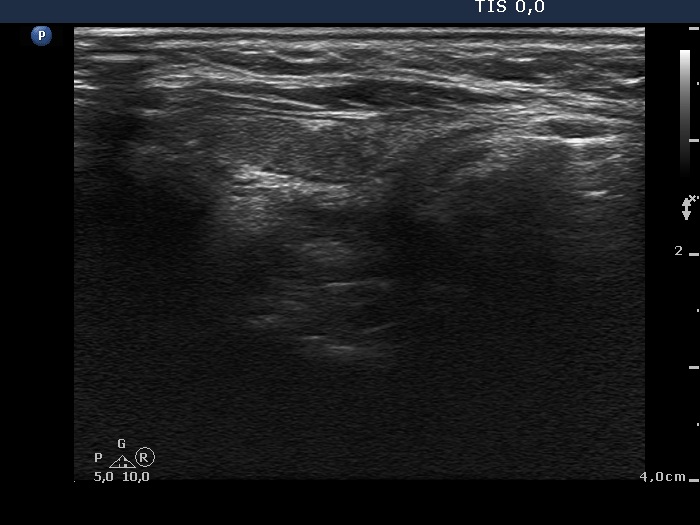

Ultrasonography. The right thyroid was moderately hypoechogenic without any circumscribed lesions. The left thyroid was removed. There were several enlarged lymph nodes in the right submandibular area. The largest one presented two discrete, more hypoechogenic intranodal lesions and a regular hilum.

Comment. This is an unusual case, the nodes (particularly those presented in the video) seem to be benign, reactive-type ones.